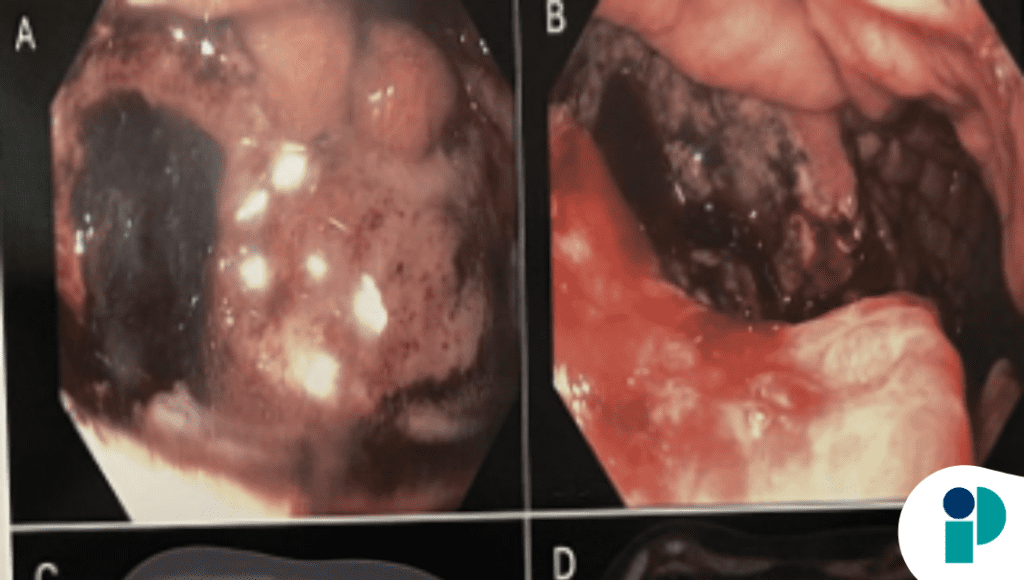

La resonancia magnética ambulatoria identificó una gran masa intraabdominal de origen incierto entre páncreas y pared gástrica posterior. Posteriormente, la endoscopia digestiva alta reveló una masa ulcerada y necrótica extensa, con compromiso del cardias, fundus y curvatura mayor gástrica, hallazgo que elevó la preocupación por malignidad avanzada.